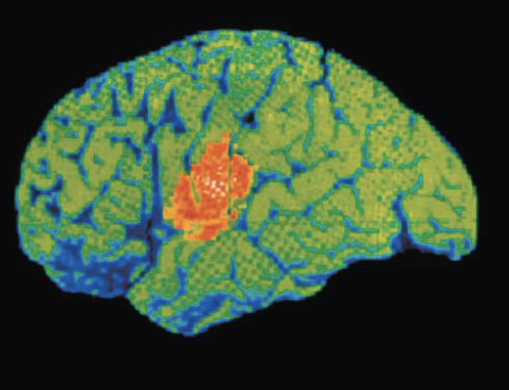

Functional imaging (PET and MRI) of brain show specific motor and sensory functions are located in discrete cortical areas called domains

Cerebral Cortex

Motor areas

Located in frontal lobe, motor areas act to control voluntary movement

Primary (somatic) motor cortex

Located in precentral gyrus of frontal lobe

Pyramidal cells: large neurons that allow conscious control of precise, skilled, skeletal muscle movements

Pyramidal (corticospinal) tracts: formed from long axons that project down spinal cord

Somatotopy: all muscles of body can be mapped to area on primary motor cortex